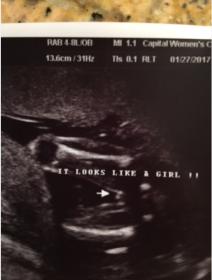

19 weeks gender - doctor 97

Yesterday we had our anatomy scan at 19 weeks, our baby was being very stubborn and wouldn't uncross their legs most of the scan. The doctor believes she got the right picture to determine gender and said she is 97% sure. We had a gender reveal last night and are over the moon about the baby being a GIRL. I had a feeling it was a boy so i was in complete shock. But now that i keep looking at the picture i am very nervous it could actually be a boy and she was wrong. I don't want to start buying to much stuff if she is wrong. If anyone could please give me their thoughts it would be greatly appreciated!!!!